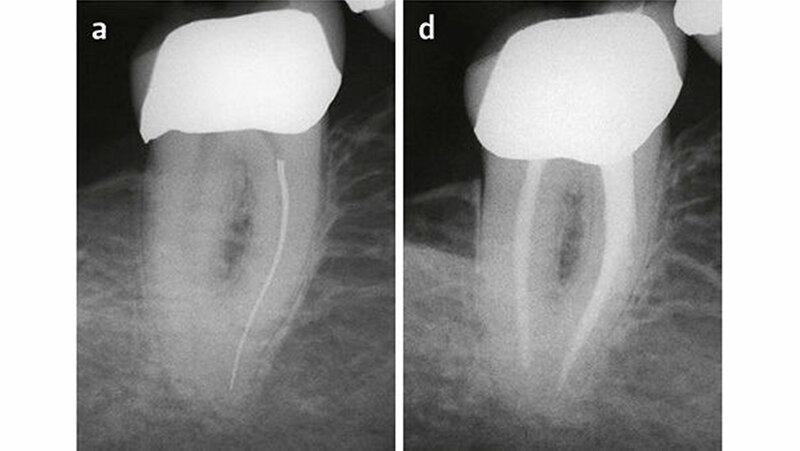

Anschließend kann es mittels Ultraschallspitzen oder feinster Trepanbohrer umfahren und allenfalls gelockert werden (Ward et al. 2003) (Abb.1). Falls das Instrument trotz Ultraschallvibration nicht aus dem Kanal hinausbefördert wird, bietet sich die Möglichkeit, es in einer Hohlnadel zu verkeilen oder zu verkleben und herauszuziehen (Suter 1998; Schutz-Bongert & Tulus 2016) (Abb. 2). Dabei ist es manchmal schwierig, die zueinander passenden Dimensionen von Hohlnadeln und Hedströmfeilen zum Verkeilen des Fragments zu finden. Alternativ kann das Instrument nach 'Bypassing' (s.o.) oft mittels Ultraschall oder Handinstrumenten aus dem Kanal hinausbefördert werden.